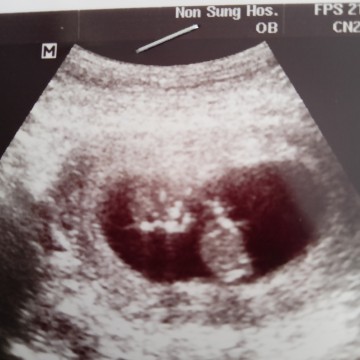

แม่ๆคนไหนมีภาพอัลตร้าซาวด์ประมาณ13วีคบ้างคะ ของเรา13วีค ภาพแบบนี้ค่ะ ดูไม่ออกเลย?

ตอน11วีคจ้า